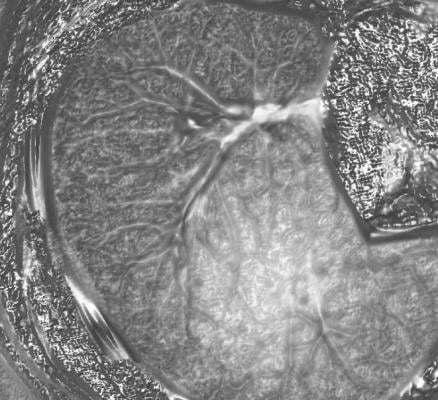

May 22, 2012 — Peter B. Bach, M.D., of the Memorial Sloan-Kettering Cancer Center, New York, and colleagues conducted a systematic review to examine the evidence regarding the benefits and harms of low-dose computerized tomography (LDCT) screening for lung cancer, which is the leading cause of cancer death. "Most patients are diagnosed with advanced disease, resulting in a very low 5-year survival rate," the authors write. "Renewed enthusiasm for lung screening arose with the advent of LDCT imaging, which is able to identify smaller nodules than can chest radiographs."

For the review, the researchers identified 8 randomized controlled trials and 13 cohort studies of LDCT screening that met criteria for inclusion. Three randomized studies provided evidence on the effect of LDCT screening on lung cancer mortality, of which the National Lung Screening Trial was the most informative, demonstrating that among 53,454 participants enrolled, screening resulted in significantly fewer lung cancer deaths (20 percent lower relative risk). The other 2 smaller studies showed no such benefit. "In terms of potential harms of LDCT screening, across all trials and cohorts, approximately 20 percent of individuals in each round of screening had positive results requiring some degree of follow-up, while approximately 1 percent had lung cancer. There was marked heterogeneity in this finding and in the frequency of follow-up investigations, biopsies, and percentage of surgical procedures performed in patients with benign lesions." The authors write that "Low-dose computed tomography screening may benefit individuals at an increased risk for lung cancer, but uncertainty exists about the potential harms of screening and the generalizability of results."